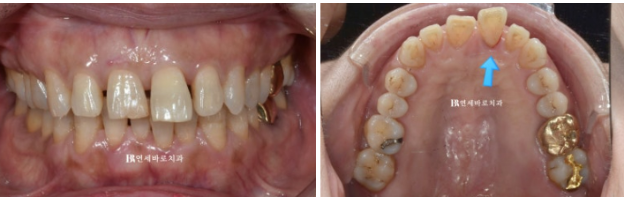

오늘은 60대 환자분이 6개월 만에 인비절라인으로 벌어진 치아를 말끔하게 교정한 사례를 보여드리겠습니다.

치아가 점점 벌어져서 오시는 경우 단기간에 급속도로 벌어졌다면 노화가 아닌 잇몸염증 때문인 경우가 많습니다.

특히 사진처럼 염증이 있는 치아는 점점 앞으로 돌출이 될 뿐아니라 아래로도 내려오게 됩니다.

그래서 벌어짐의 이유가 잇몸염증 때문이라면 교정치료 전 잇몸 염증 치료를 먼저 해야 합니다.

꼼꼼한 잇몸치료 후 인비절라인 교정 치료에 들어갔습니다.

어금니 교합은 원래 좋은 편이여서 전략적으로 원래 교합을 유지하면서 치료를 진행했습니다.